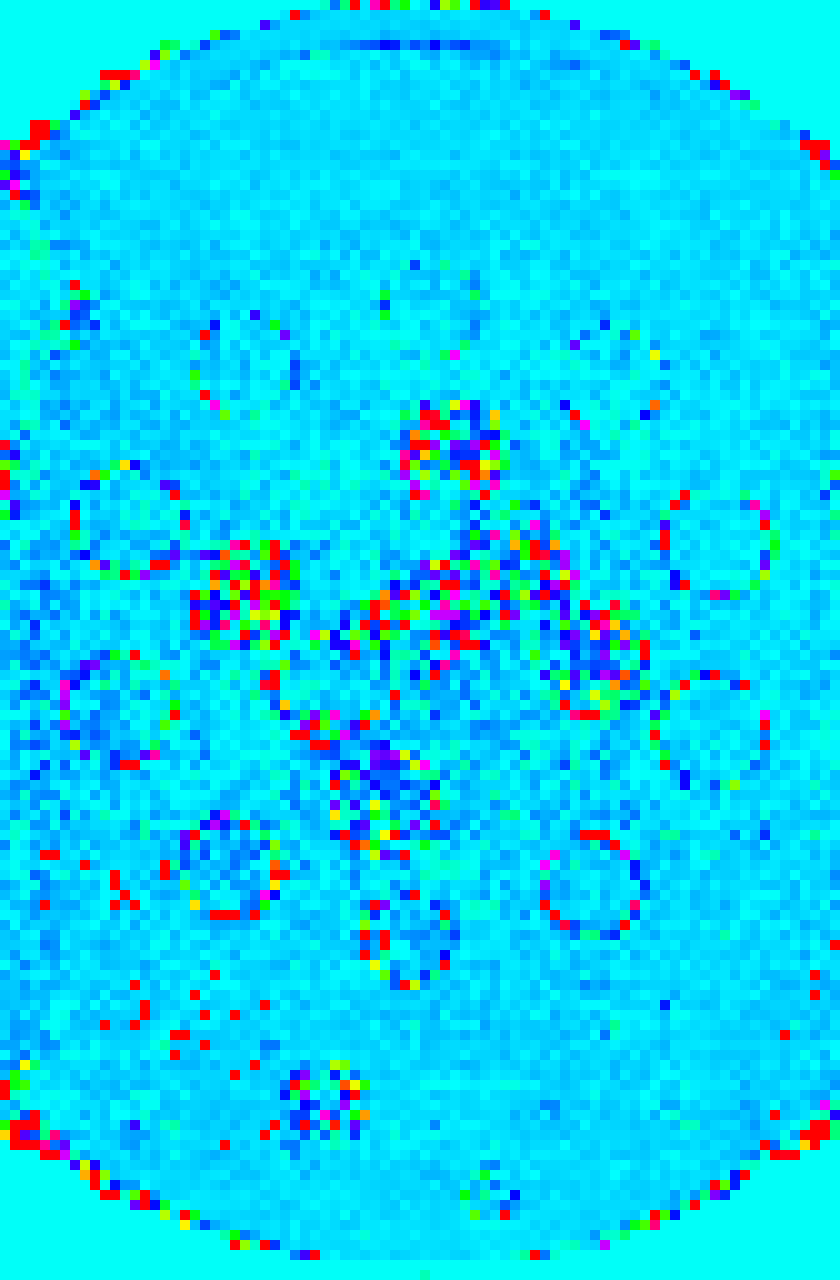

Refer to caption

(a) Full-size magnitude of M0subscript𝑀0M_{0} map

(b) Downsampled magnitude of M0subscript𝑀0M_{0} map

(c) Full-size phase map of M0subscript𝑀0M_{0}

(d) Downsampled phase map of M0subscript𝑀0M_{0}

(e) Full-size T1subscript𝑇1T_{1} map (ms)

(f) Downsampled T1subscript𝑇1T_{1} map (ms)

(g) Full-size T2subscript𝑇2T_{2} map (ms)

(h) Downsampled T2subscript𝑇2T_{2} map (ms)

Fig. 2: The ground truth maps acquired from a fully sampled acquisition of the Eurospin II TO5 phantom used in the Monte Carlo simulations are shown on the left, and downsampled version of the map for computation of TEUSQA is shown on the right.

The 𝜽𝒙GTsuperscriptsubscript𝜽𝒙𝐺𝑇\bm{\theta}_{\bm{x}}^{GT} and C𝒙,cGTsubscriptsuperscript𝐶𝐺𝑇𝒙𝑐C^{GT}_{\bm{x},c} were downsampled to |Ωx,D|=24×24superscriptΩ𝑥𝐷2424|\Omega^{x,D}|=24\times 24 by applying nearest-neighbor interpolation on each parameter map separately while undersampling patterns were generated specifically for Ωx,DsuperscriptΩ𝑥𝐷\Omega^{x,D}. Both the original and downsampled ground truth maps are shown in Figure 2. The ROI mask was obtained by applying the same downsampling operation to 𝜽𝒙GTsuperscriptsubscript𝜽𝒙𝐺𝑇\bm{\theta}_{\bm{x}}^{GT}, to the ROI mask used for Monte Carlo simulation. The ηpsubscript𝜂𝑝\eta_{p} for each voxel corresponding to voxels in the full-size map where nominal values are available was computed according to Equation 14.